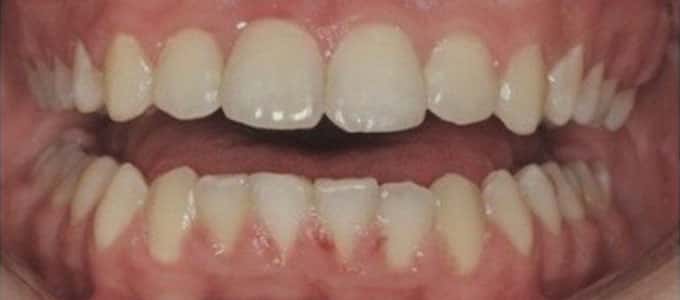

Un zâmbet frumos

Un zâmbet frumos este roada tratamentului ortodontic de succes dar pentru a se ajunge la acest rezultat sunt necesare mai multe etape care trebuie parcurse pas cu pas.

Tratamentul ortodontic este un proces biologic complex care include modificări ale oaselor maxilare, faciale și ale țesuturilor moi pe măsură ce dinții sunt mișcați în noile poziții.